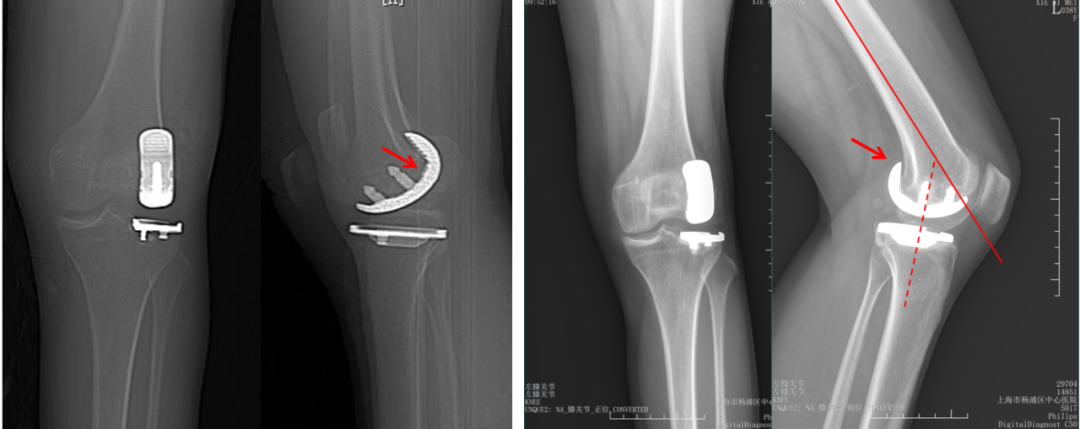

胫骨假体内翻

AP位胫骨与股骨假体位置:胫骨假体内翻10°,股骨假体中轴线与胫骨假体垂直。

胫骨假体后倾角大

侧位胫骨假体位置:胫骨假体后倾11°,前后缘齐平。

胫骨假体前倾

侧位胫骨假体位置:胫骨假体前倾5°,前后缘齐平。

股骨假体后倾不足

侧位股骨假体位置:股骨假体后倾5°,后髁包容不足。